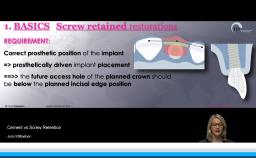

Dental implants are designed to provide support, stability, and retention for dental prostheses. In addition, implants have evolved to enable optimal esthetic and functional outcomes for patients seeking dental rehabilitation for a variety of indications. This lecture focuses on optimizing prosthodontic outcomes for patients via a systematic and evidence-based team approach to treatment. This includes contemporary treatment planning with an emphasis on communication of ideal implant placement; choice of implants, components, and restorative biomaterials to minimize complications; and prosthesis design and maintenance options to enhance longevity.

- recognize contemporary implant and prosthodontic components and their influence on ability to achieve optimal prosthodontic outcomes